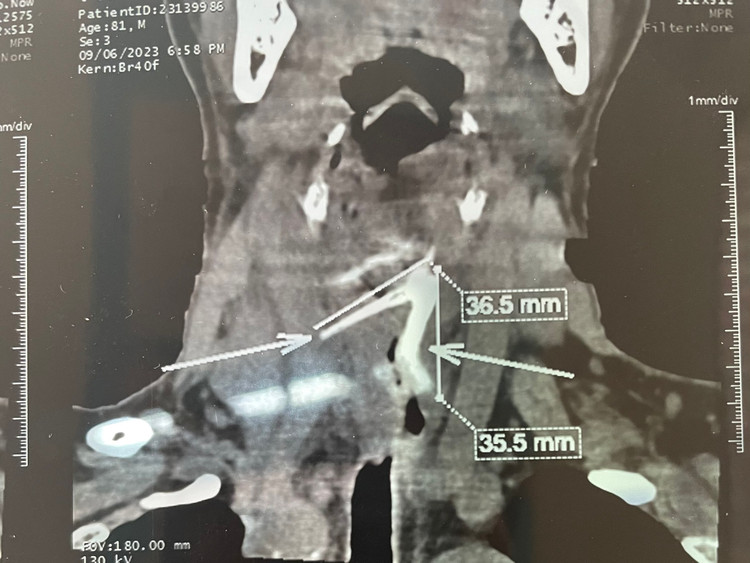

| Hình ảnh xương hóc trên phim chụp |

Bệnh nhân nhập viện trong tình trạng bị nhiễm trùng nặng có ổ mủ do thực quản bị thủng, bị áp xe cạnh thực quản. Bệnh nhân được chỉ định chụp CT scan và phát hiện dị vật xương dài khoảng 3cm. Sau khi phẫu thuật lấy xương và điều trị nhiễm trùng, hiện sức khỏe bệnh nhân đã ổn định, đã cho xuất viện trong ngày 11/9.